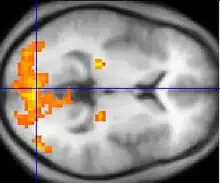

Il s'agit de la capture par une IRM de séquences spécifiques : des séquences echo-planar T2* (ce sont des séquences d'IRM spécifiques) permettant de mettre en évidence le signal BOLD. On obtient ainsi pour chaque voxel une valeur du signal Bold, l'ensemble des voxels correspondant à ce qui est appelé cartes paramétriques. La comparaison statistique des cartes paramétriques seuillées permet de créer des cartes d'activation. Lorsque ces cartes d'activation sont superposées à une IRM cérébrale standard, on obtient l'image classique d'une IRM fonctionnelle (cf l'image en début d'article). L'étude statistique plus poussée de ces cartes d'activation peut permettre de faire de la connectivité fonctionnelle, c'est-à-dire de faire un lien entre différentes zones cérébrales utilisées lors d'une même tâche.